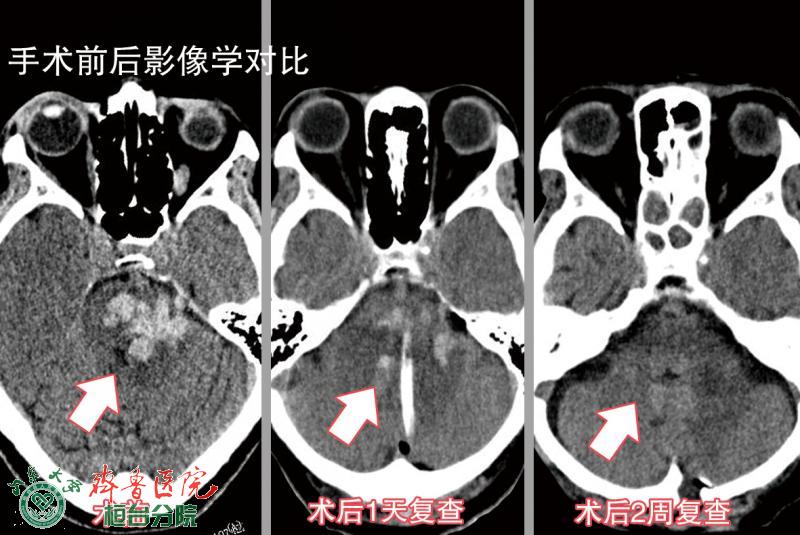

近日,齐鲁医院桓台分院神经外科利用方体定位技术打破了脑干手术的禁区,成功抢救了一名脑干出血10ml的病人。

手术在急诊局麻加强化下行方体定位引流术,定位、钻孔、血肿穿刺、引流等各项技术在紧张有序的操作中顺利完成,脑干和破入脑室的血液被成功引流,总计约9毫升。

术后,宋奎勤副主任及他的医疗团队,又给予赵女士以抗炎、预防消化道出血、营养神经、补液等治疗,患者病情逐渐好转,2天后神志恢复清醒,也可以经口进食,3天后患侧上肢产生自主活动,20天后,赵女士要求出院,回家继续进行康复锻炼。(宋立坤)